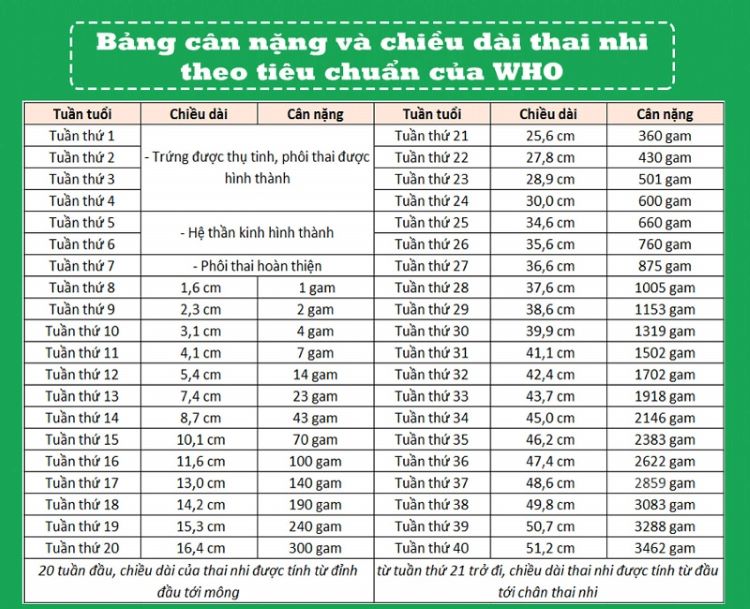

Bảng cân nặng của thai nhi đạt chuẩn theo tuần

Ở thời điểm trước tuần thứ 8, phôi thai lúc này đang trong giai đoạn hoàn thiện. Nên khi đó quá trình siêu âm chỉ thấy một chấm nhỏ nên cân nặng và chiều dài đầu mông, lúc này sẽ xác định sau thời gian này. Để theo dõi quá trình lớn lên của con, các mẹ có thể theo dõi bảng cân nặng thai nhi theo tuần dưới đây:

Bảng cân nặng của thai nhi theo tuần

Không nhất thiết cân nặng của thai nhi phải đạt được con số chính xác như trong bảng. Do đó, mẹ bầu không cần quá căng thẳng về những thay đổi nhỏ trong các chỉ số của em bé.

Mỗi thai nhi sẽ có một tốc độ phát triển khác nhau. Cân nặng trung bình của bé trai và bé gái khi sinh ra đủ tháng sẽ là 3,5kg. Với chiều dài đạt 51,2 cm. Dưới đây sẽ là hướng dẫn cách đo theo từng tuần tuổi để bạn tham khảo:

Thời kỳ tam cá nguyệt I (từ tuần thứ 8 đến 19): Chiều dài của thai nhi được tính từ đầu đến mông. Hay còn gọi là CRL (tức chiều dài đầu mông). Thai nhi trong giai đoạn này thường rất nhỏ nên bác sĩ rất khó xác định trọng lượng chính xác.

Thời kỳ tam cá nguyệt II (từ tuần 20 đến 42): Bác sĩ sẽ đo từ đầu đến gót chân của bé. Như vậy sẽ xác định được chiều dài, đo đường kính đỉnh đầu. Và chu vi vòng bụng và chiều dài xương đùi thai nhi để tính toán được cân nặng chính xác.

Thời kỳ tam cá nguyệt III (từ tuần thứ 32 sau): Bác sĩ sẽ tiếp tục sử dụng những thông số như cách đo kì tam cá nguyệt II. Đồng thời kết hợp với một số yếu tố khác để tính toán trọng lượng của thai. Đây là giai đoạn mà cân nặng thai nhi phát triển nhanh, các đường nét trên cơ thể dần hoàn thiện.